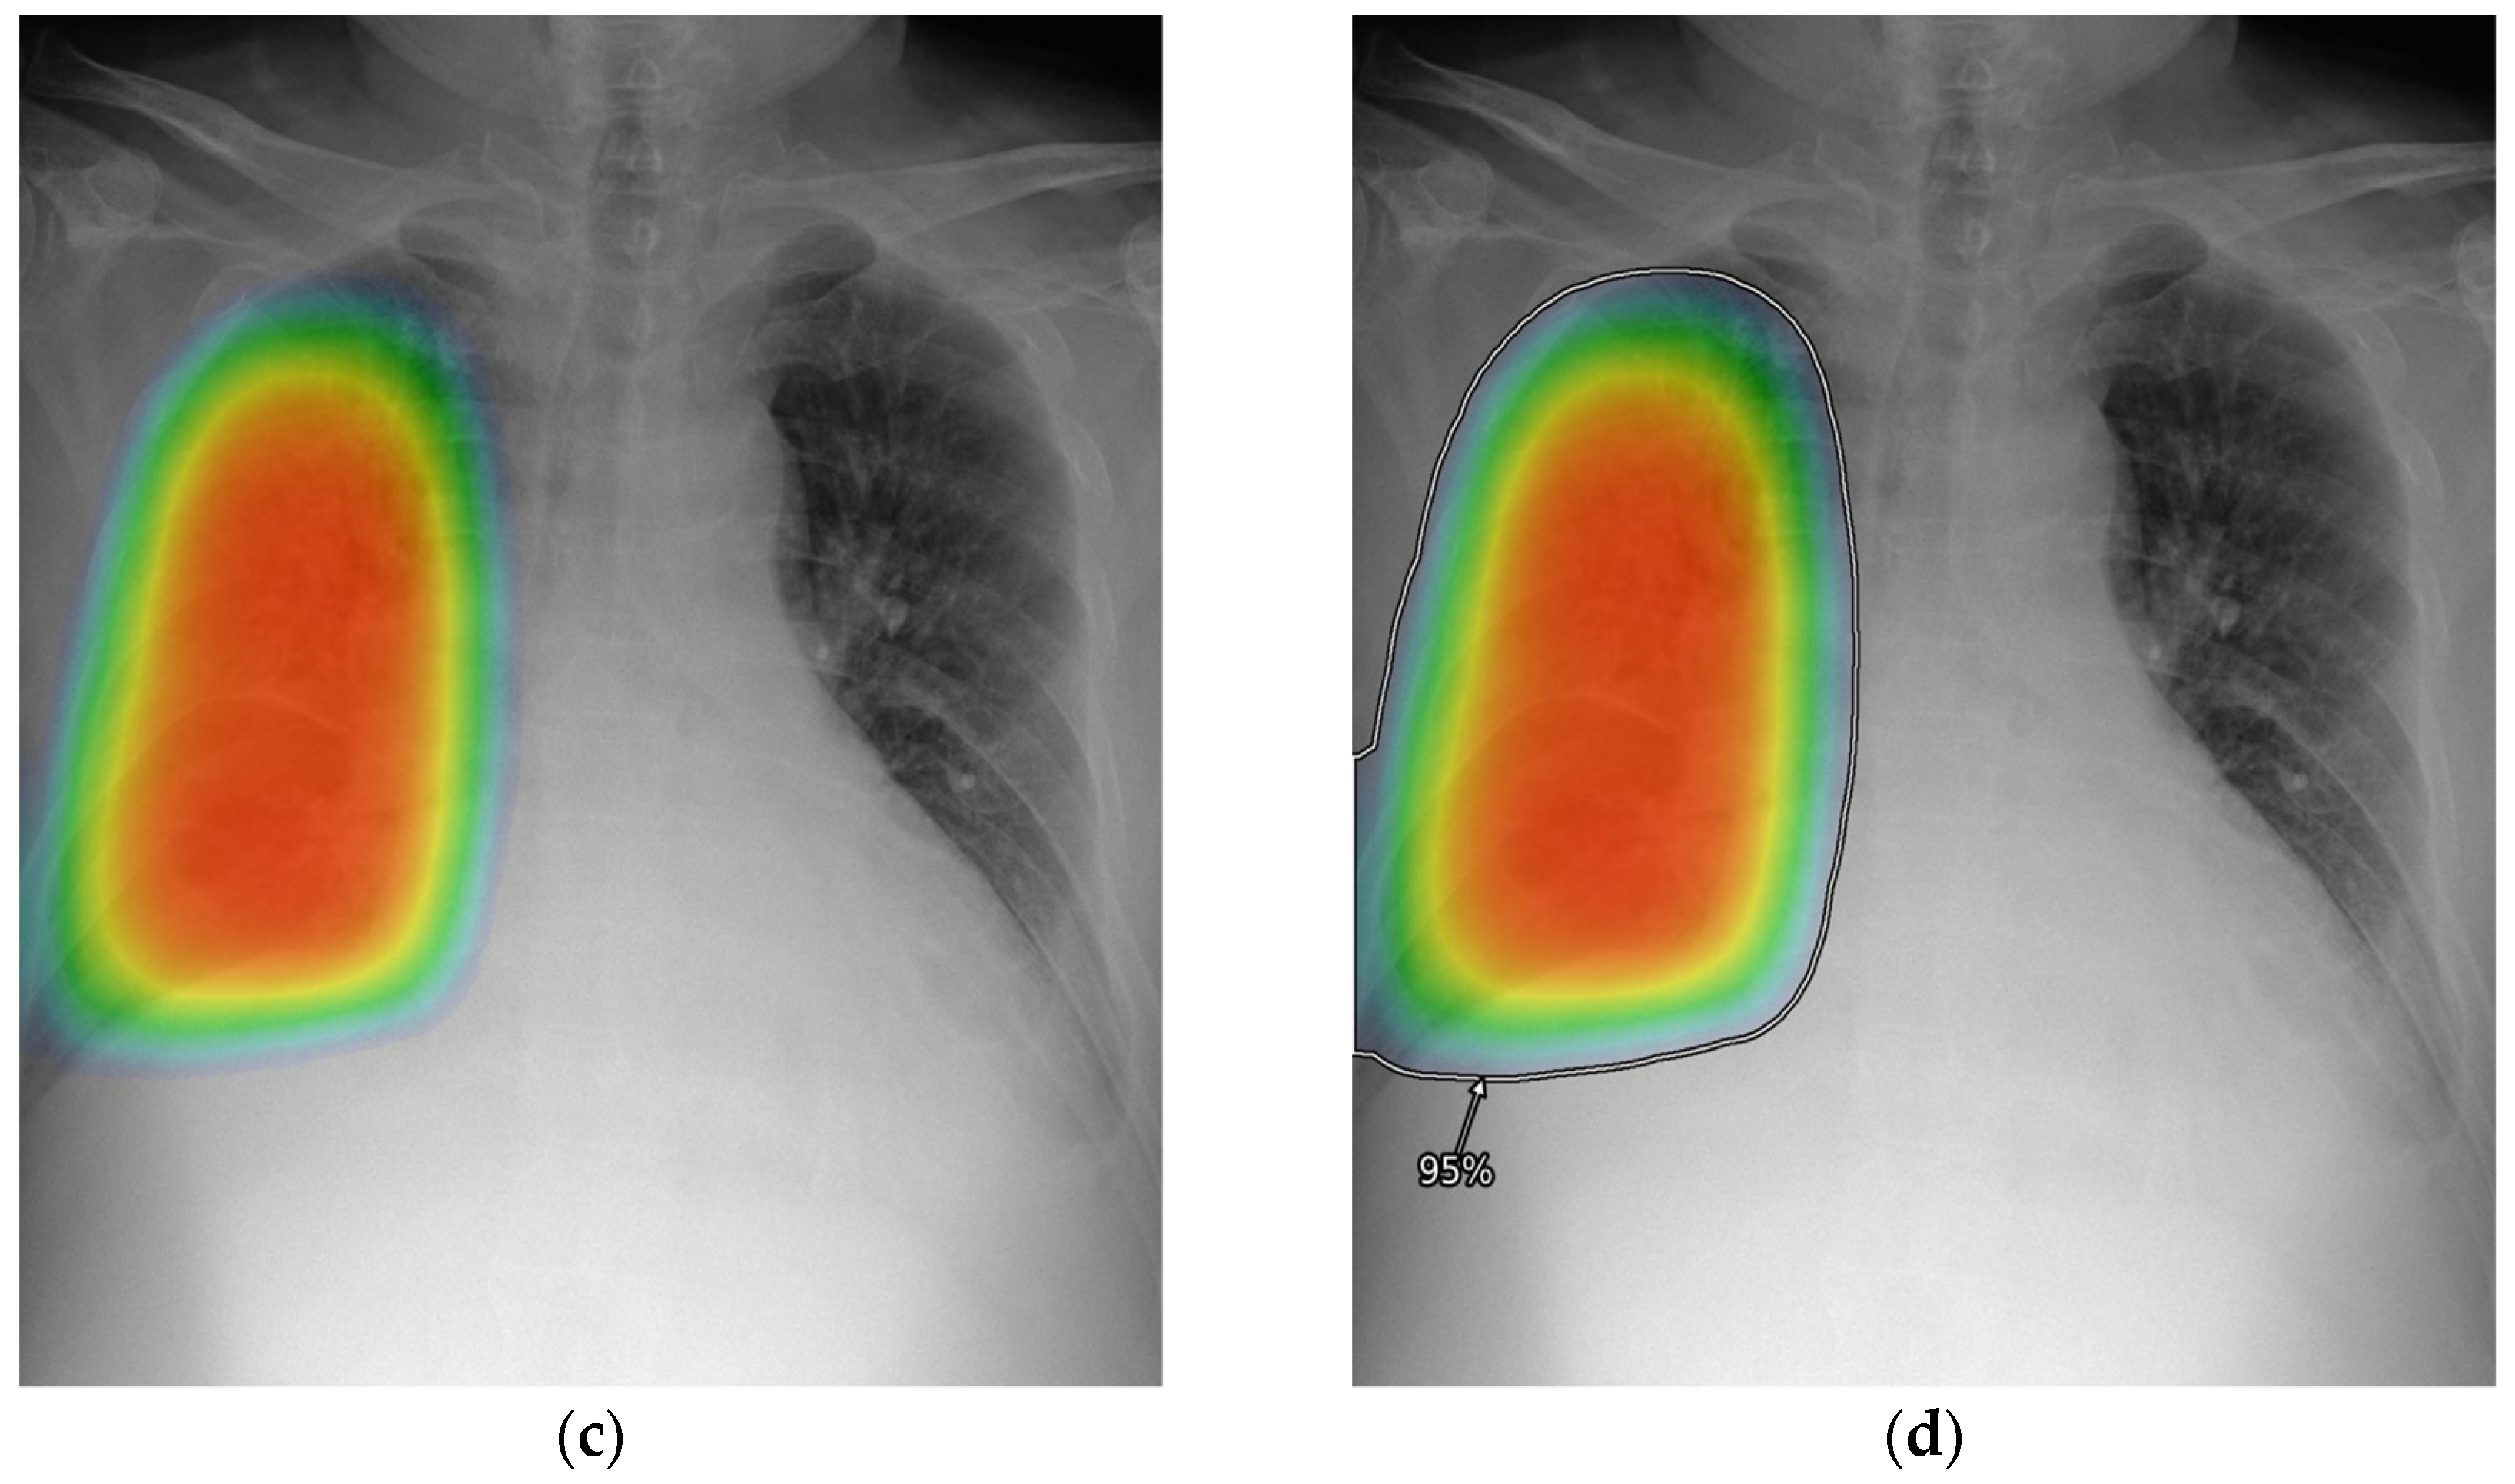

2.4. Reader Test